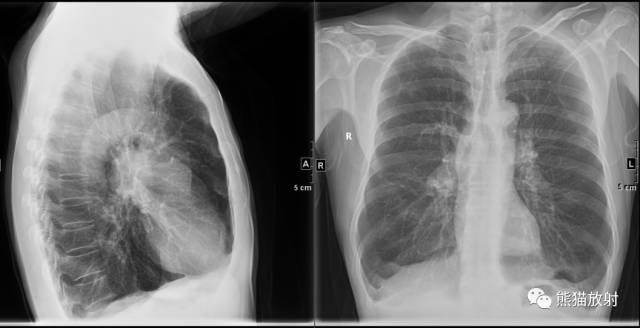

| 间隔旁型肺气肿 |

小叶中心型、全小叶型及间隔旁肺气肿常见于慢性支气管炎、各种原因的肺间质纤维化及支气管哮喘等。小叶中心型(需CT诊断)及全小叶型肺气肿可融合成大泡。

肺大泡是因小支气管活瓣性阻塞,肺泡过度膨胀、破裂互相合并而成,其直径大于1cm。肺小泡是指脏层胸膜内的积气,其直径最大1cm。

肺大泡X线表现为:薄壁环形透光区,壁薄如线,常只能见到部分囊壁,甚至有时不易见其囊壁,只见局限性透亮区,其中无结构。巨大的肺大泡可压迫周围肺组织,使囊壁增厚。

肺大泡可单发或多发,大小不一,多位于肺的周边,以肺尖、肺底常见。较小的大泡CT可明确显示。成年人进行性巨大肺大泡,称为肺消失征。肺大泡即可见于弥漫型肺气肿,亦可见于局限性阻塞性肺气肿。